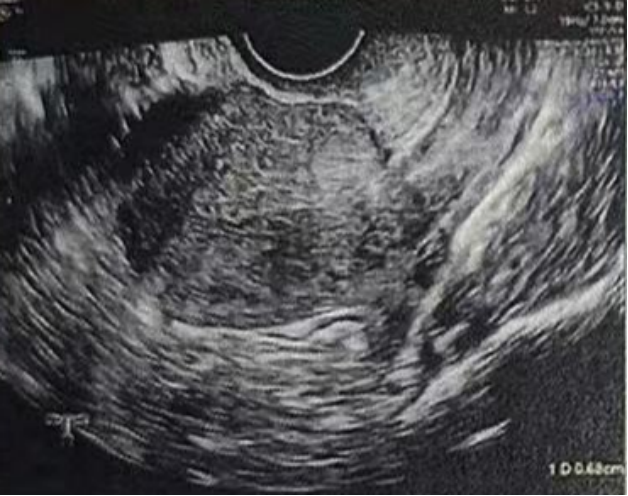

• 阴超检查:基础卵泡 6 颗

- 右侧卵泡 2 颗 (3-4mm)

- 左侧卵泡 4 颗 (3-5mm)

阴超检查:

- 右侧卵泡 2 颗

- 左侧卵泡 6 颗

- 右侧卵泡 2 颗 (10,20mm)

- 左侧卵泡 5 颗 (20,18,12,7,7mm)